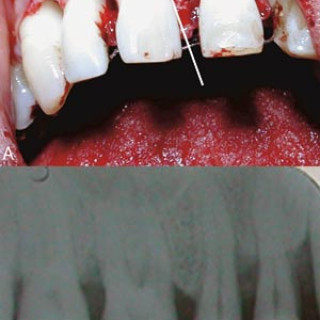

En 23 år gammel førstegangsgravid kvinne som fra tidligere stort sett var frisk, ble innlagt i lokalsykehus ved svangerskapslengde 22 uker + 2 dager, med en seks dagers sykehistorie med generell sykdomsfølelse, feber opptil 40 °C, kvalme, oppkast og anoreksi. I tillegg hadde hun fått økende ansiktsødemer, korsryggssmerter, hodepine og synsforstyrrelser. Svangerskapet hadde vært ukomplisert frem til det aktuelle. Hun var normotensiv. Blodprøvene viste kreatinin 236 µmol/l, karbamid 13 mmol/l, urat 410 µmol/l, leukocytter 15,0 · 10⁹/l, CRP 106 mg/l og trombocytter 86 · 10⁹/l. Leverprøvene var...